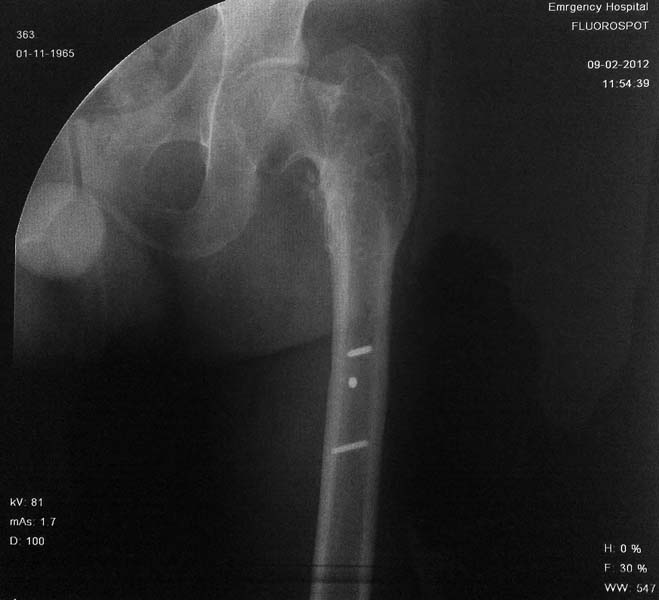

Рентгенограмма пациента А 49 лет с диагнозом: Неправильно консолидированный подвертельный перелом левой бедренной кости, с варусной деформацией.

На рентгенограммах левого тазобедренного  сустава шеечно-диафизарный угол 90 градус. Признаки артроза 2 ст и очаг остеосклероза  в проекции ШДУ (указан стрелкой).

Имя     : ap.jpg